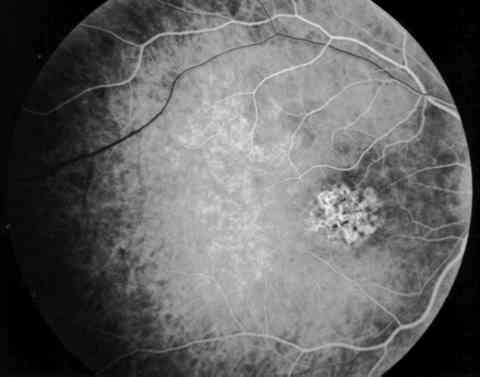

Figura 6

AFG. ESTADIO ARTERIO-VENOSO.